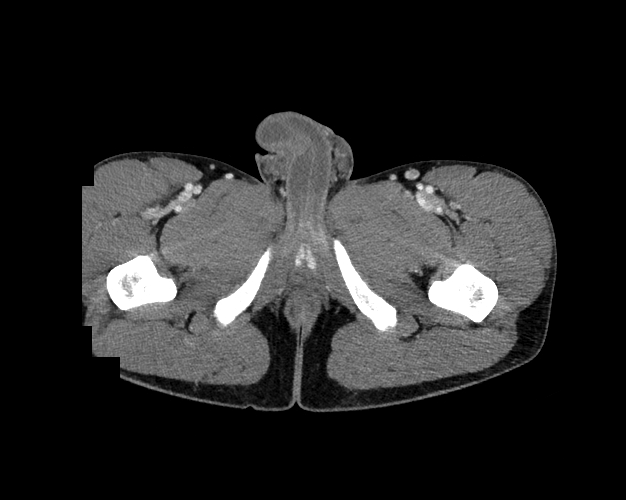

Body

Covers abdominal CT anatomy.

Pelvis

Covers pelvic MRI anatomy.